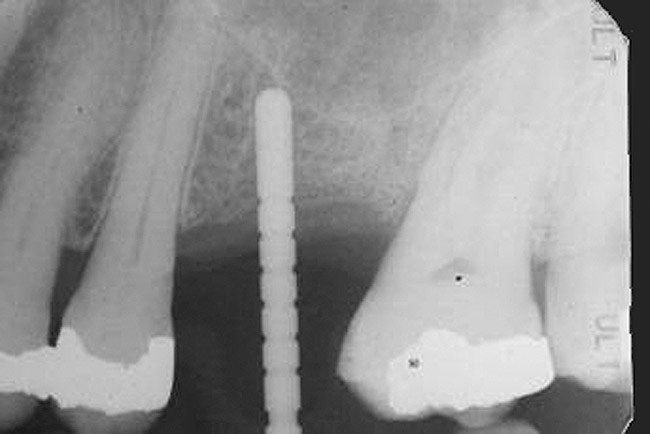

With a 2-mm twist drill in the handpiece, the head of this tool is aimed at the opposite jaw to attain the proper angulation for drilling the osteotomy. The initial development of the osteotomy with the 2-mm drill should be done to a depth of approximately 5 mm, and then a guide pin should be placed to assess osteotomy angulation (Figure 8).29 At this juncture, alterations in angulation can be done with the twist drill. Also, guide pins can be placed into multiple osteotomies to assess parallelism between implants and/or adjacent structures. At this early stage, parallelism should be adjusted as necessary.

When a 2-mm twist drill is used to full depth of the osteotomy (eg, 10 mm), it is difficult to change osteotomy angulation with a twist drill. If a correction is necessary, a side-cutting bur (eg, Lindemann) should be used (Figure 9). Furthermore, if there are doubts as to closeness of the osteotomy to adjacent teeth or vital structures, then a radiograph with a guide pin in place should be obtained.30 Ultimately, the angulation and location of the osteotomy should be consistent with design of the future restoration.31